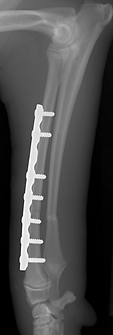

Fractures can be treated using a variety of methods, depending on severity, location, and patient factors. Options include:

Surgical repair may use plates and screws, rods or nails, or external fixators. Decisions depend on location, configuration, displacement, soft tissue condition, patient age, and underlying bone health. Prompt treatment is preferred, though life-threatening injuries always take priority. Postoperative care is critical to prevent implant failure and ensure healing.